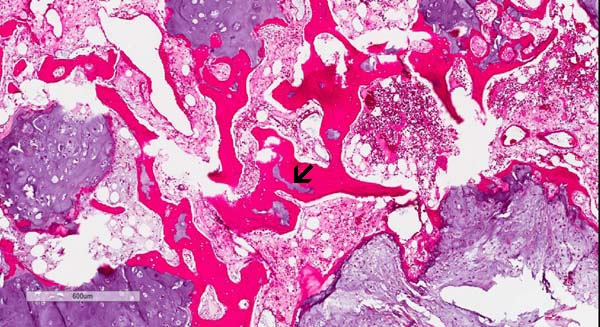

On the histologic slide, this tumor is composed of a low-grade

neoplastic chondroid of low cellularity. The overall cytologic

features are reminiscent of normal cartilage but they are separated

into numerous lobules separated by thin fibrovascular bands.

These lobules can vary from one to several millimeters in diameter.

The tumor bulge out and disrupted the cortical bone.

-

In another location of the tumor, there is definitive

invasion

of the haversian system. This is an important features for the

diagnosis of chondrosarcoma.